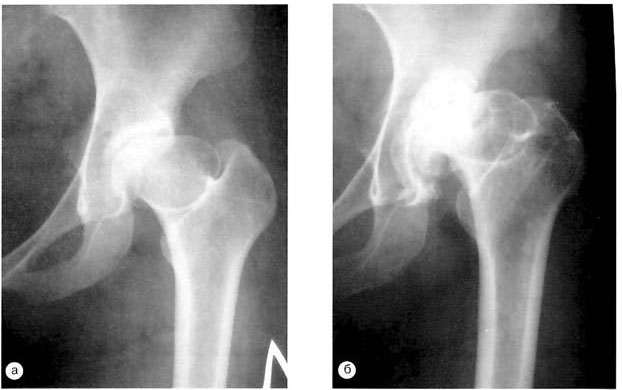

Остеопороз является одной из самых частых причин возникновения патологического перелома бедренной кости. На его фоне описываемое повреждение чаще всего возникает у женщин постклимактерического возраста – как правило, это повреждение шейки бедренной кости.

- рентгенологическое обследование – оно имеет наибольшее значение в выявлении патологического перелома бедренной кости. Делают снимки в двух проекциях, на них выявляют линию перелома, смещение отломков (если оно имеется);

- компьютерная томография (КТ) – привлекается в спорных случаях. Компьютерные срезы помогут оценить состояние костной ткани больше, чем рентгенография;